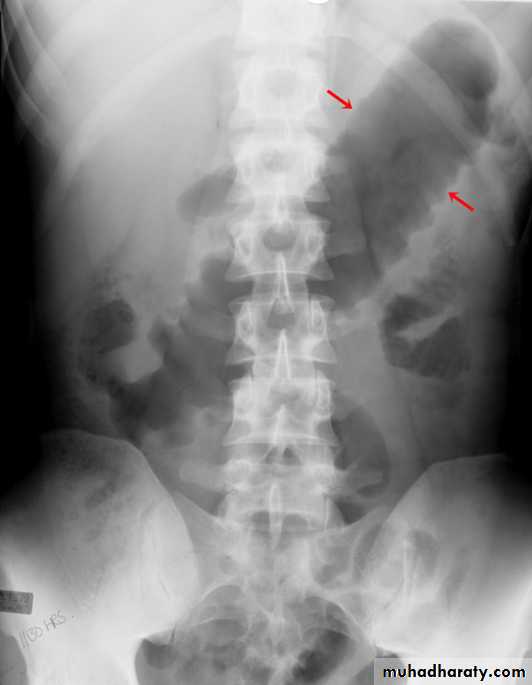

apple core lesion in the descending colon

Multiple lesions are seen in the liver and spleen consistent with metastases

Ba enema

• Morphological types:• 1_ Ulcerative : give rise to irregularity of the colon with ulceration.

• 2_ Constrictive or infiltrative ( Annular ) type :

• a- Constant narrowing .

• b-Shouldering sign, apple core sign .

• c- Destruction of mucosa at narrow area .

• d- Double track due to fistula .

• e- In severe constriction ; stoppage of Ba. Flow with proximal dilatation .

3_Proliferative type : give rise to :

a- Large , constant filling defect with irregular margin .

b- Destruction of mucosa .

c- Intestinal obstruction